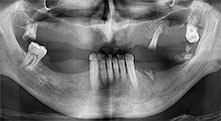

Restbezahnung

Ein 40-jähriger Patient mit desolater Restbezahnung wünscht eine Implantatversorgung. Da er Raucher ist, wird im Oberkiefer kein Sinuslift mit festem Zahnersatz, sondern eine Stegprothese auf vier anterioren Implantaten geplant.